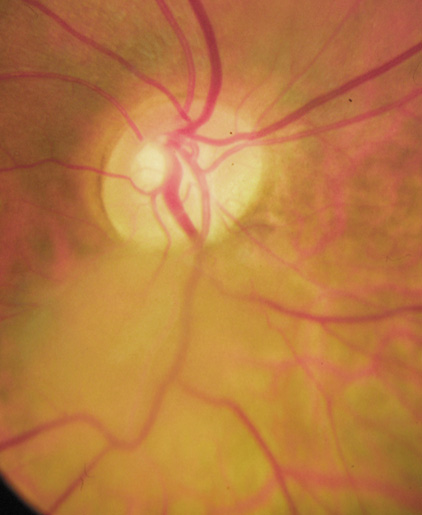

Lisch nodules are hamartomas (a tumor involving only those tissue elements normally found at the involved site) of the iris pigment epithelium. They are dome-shaped discrete lesions, are typically light brown in color, and may also be found in the angle.38 Lisch nodules appear earlier (33% at 2.5 years, 50% at 5 years of age)39 than neurofibromas. They are benign and can help to confirm diagnosis in children who may have café au lait spots as the only other clinical finding. Lisch nodules are present in nearly all adults with NF139,40 but are rare in NF2 (Fig. 3).41,42 Diffuse nodular iris nevi (also known as iris mamillations) should not be confused with Lisch nodules. Its clinical significance is not well established.43,44

|

- At least two Lisch nodules (Fig. 3)